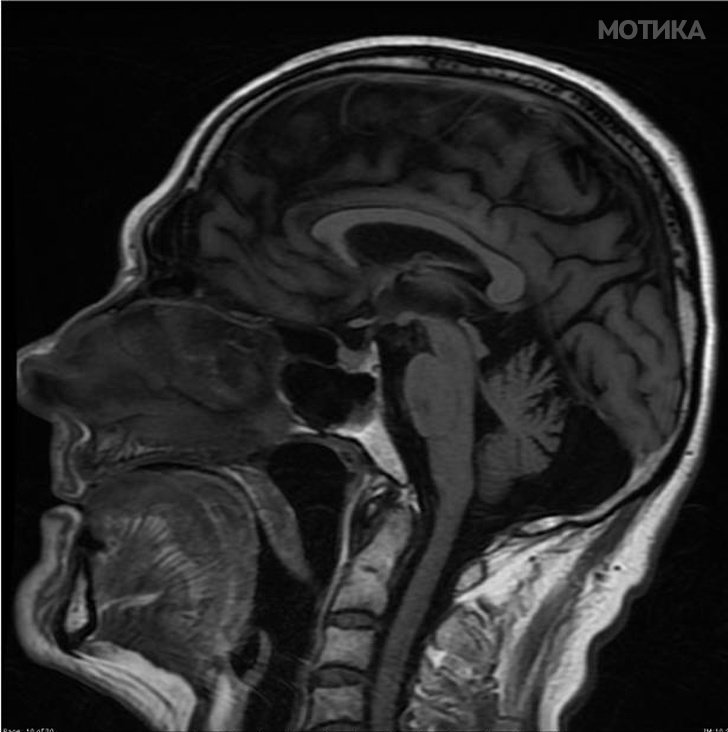

13. Пациент со алкохолно оштетување на мозокот. Мозокот и малиот мозок се намалија во големина поради изложеност на алкохол.